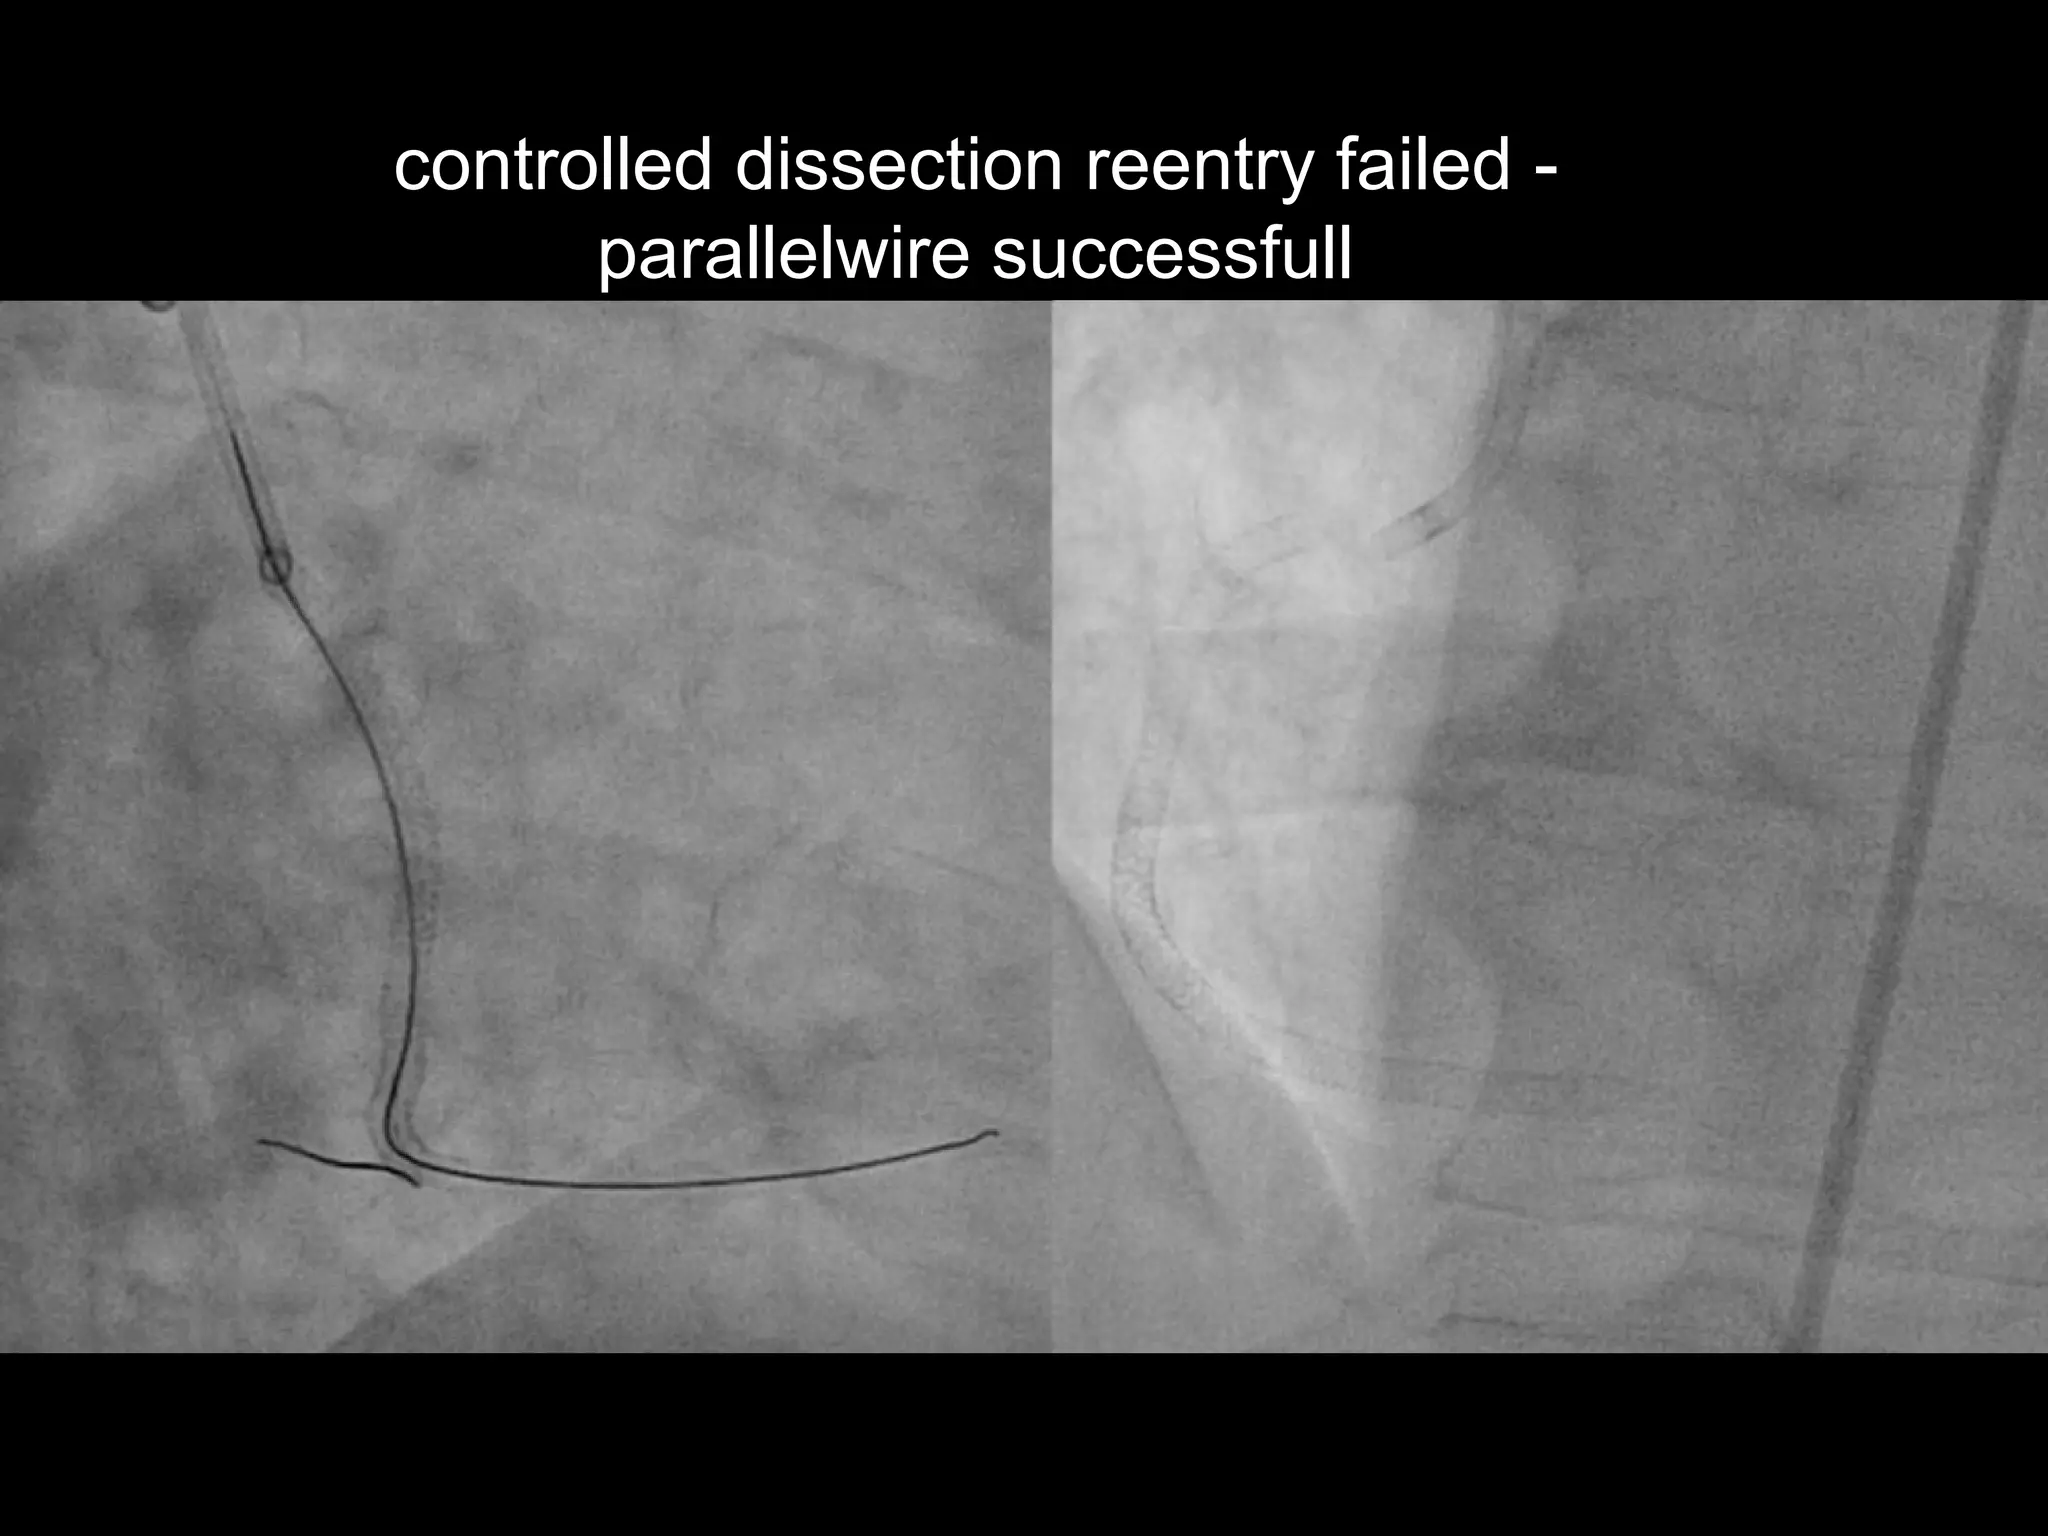

controlled dissection reentry failed -

parallelwire successfull